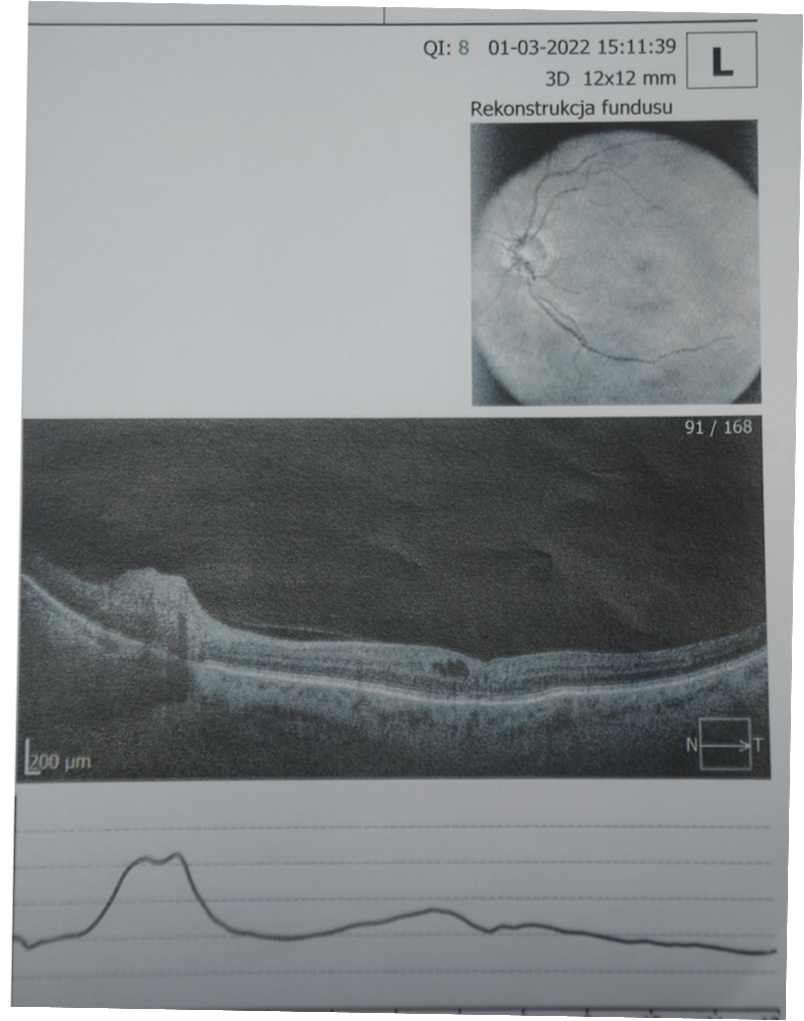

Przed przeprowadzeniem tego eksperymentu na sobie zgłosiłem się do okulisty, który wykonał badania komputerowe, co pokazuje rycina poniżej. Badania wykonano pierwszego kwietnia 2020 roku.

Zdjęcie 2. wykonane w marcu 2022. Widać zmniejszenie się odwarstwienia, a właściwie powrót do normy, czyli tak jak było przed chorobą.